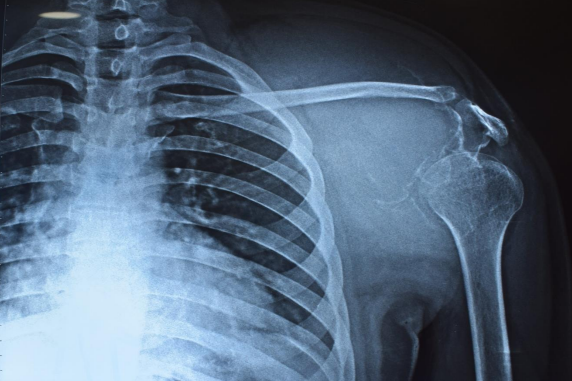

31 cases of fibromatosis were found in our database, which has data on over 10,000 patients, including those with benign bone tumours. Of these patients, 4 had desmoplastic fibroma of the bone, meaning that the incidence of fibromatosis in our population was 0.04%. Out of which three (75%) were men and one (25%) was a woman. The average age was 29.25 years (range: 21–35 years old). The skeletal distribution was one scapula, two pelvises, and one chest wall- rib. Fig-1.

Figure 1,2,3,4,5,6

Case 1- 21 year old male who presented with pain and swelling over the left scapular area , was diagnosed with left scapula fibromatosis underwent wide local excision of tumour in 2014 after clinico-radiological evaluation and post-op histopathology confirmed to be Intra-osseous fibromatosis, after 6 years patient presented with pain and local swelling and upon evaluation with X-ray Fig-2  and MRI which showed Hyper-intense lesion on T2 sequence measuring 11.2x14.5x11.3cm with destruction of scapula body and spine with soft tissue deep to the deltoid - coronal and axial images Fig-3 and Biopsy confirmed to have local recurrence and considering chance of recurrence again patient underwent Type 3 intra-articular scapulectomy with gross histopathology image and microscopic image Fig-4. And currently on 3 year follow up and no local recurrence.